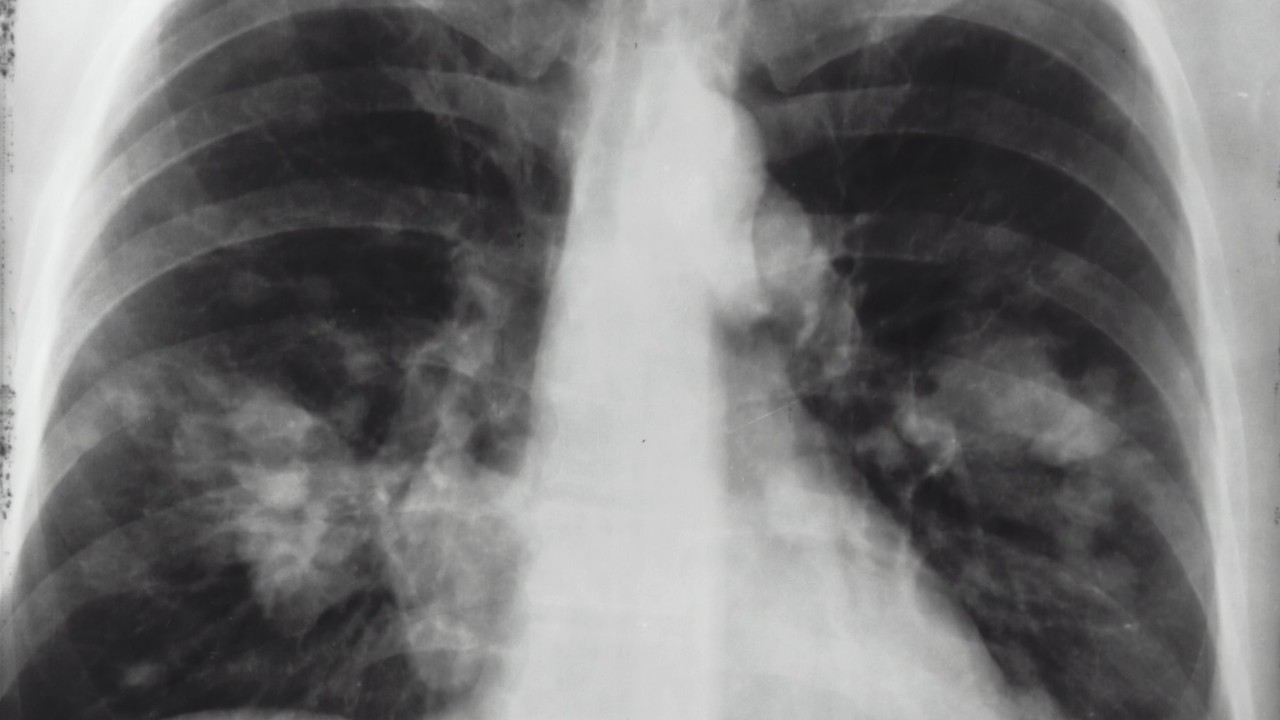

Aparece en las radiografías un pulmón de fumador

De acuerdo con la cirujana Bankhead-Kendall ha revisado muchas radiografías de tórax de casos positivos en COVID-19, los cuales se veían peor que los de un fumador habitual. Y es que entre el 70 y 80% de los contagiados asintomáticos terminan desarrollando problemas pulmonares severos.

Se indican problemas en los pulmones en las radiografías | Fuente: Pexels